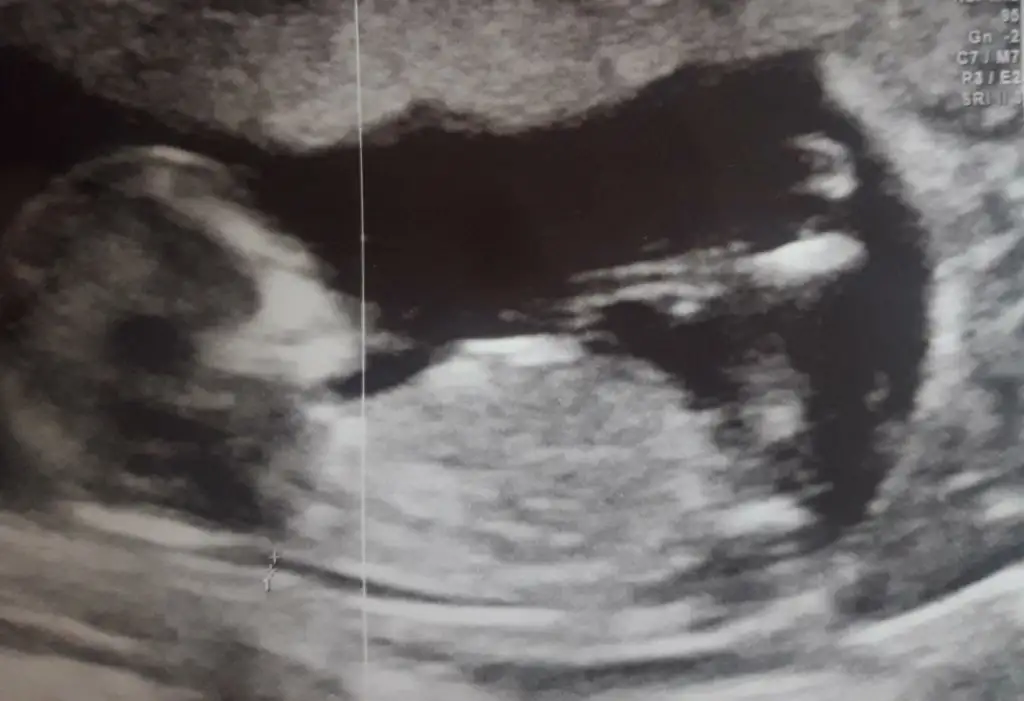

Ikra meyra Ikra meyra canım benimkine de bakabilir misin? 12+2

• A85EC690-102B-49C7-B9EA-10869B2BEC36.webp

A85EC690-102B-49C7-B9EA-10869B2BEC36.webp

32,6 KB · Görüntüleme: 78

• B9CAB7C7-D655-4766-BFC8-F19DFF013044.webp

B9CAB7C7-D655-4766-BFC8-F19DFF013044.webp

29,9 KB · Görüntüleme: 81